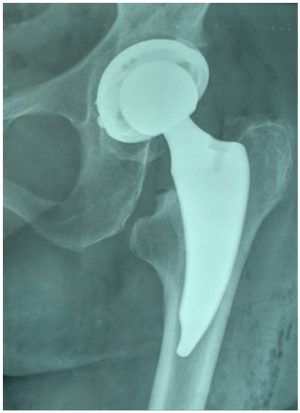

Figure 2 Zweymuller biologically fixed hip arthroplasty threaded cup.

Editorial

Some decades ago, implants of chromium, cobalt, vitale or ceramic have been tested with “Press Fit” or threaded fastening technique in the jawbone in order to replace worn teeth. From 1970 to date only screw – threaded dental titanium implants with osseointegraded surface have established because they showed very low mechanical loosening rates.1-4 The Swedish orthopedic surgeon Per-Ingvar Brånemark (1929-2014), uknown in many orthopedic societies but very well known in all dentist societies, is the father of modern dental screwed titanium implants.1,2 Brånemark began observing rabbits in the 1950s without intention of studying either titanium or dentistry. He was instead interested in the anatomy of blood flow. In one study, in 1950, (a) Titanium screwed device was inserted into the rabbits’ legs, yet when researchers tried to remove the device they found that the titanium had bonded to the bone. Further blood-related studies with titanium instruments yielded similar outcomes, and Brånemark pivoted his research to focus on titanium’s impact on the body. As more research revealed that titanium bonded to human bone consistently and for the long term, Brånemark named the phenomenon osseointegration. He started applying the concept of screwed titanium implants to dentistry, intending to help the significant portion of the population who had missing teeth. The new generation screwed implants in jawbone (Figure 1) and in acetabulum of the hip joint (Figure 2) with a grit blasted roughness surface offer even more a very stable mechanical and biological primary fixation because they have larger contact area to the bone compared to other implants of the same diameter and simple shape design and surface. So, in the hip joint, the new generation threaded acetabular titanium implants Zweymuller type5,6,7 with thin fins (lamelae) and roughened osseointegraded surface showed excellent permanent results which were found also in our long series of more than two thousand total hip replacements. Between them many dysplasia or congenital dislocation cases and this is mainly due to the similarity in shape and bone stock of the destroyed acetabulum to that of the remaining area of the jawbone after removal of a damaged tooth. At first and up to the 80’s, the main type of hip screwed cups used internationally in many orthopedic centers were mainly those of Mittelmeiyer, Link or PCA type; because of their poor results due to their anelastic, smooth and non-osseointegraded surface, the use of new generation biologically fixed screwed-threaded titanium arthroplasty cups was not widely accepted, to the opposite of the excellent acceptance of screwed-threaded titanium teeth implants. These old unsuccessful cups had only primary mechanical stability but not permanent biological fixation; they were not accompanied by enough periprothetic new bone formation and accompanied by very bad results and elevated rates of mechanical loosening. The difference between the old type and the new generation threaded hip cups is that the new generation titanium threaded cups of Zweymuller type are similar to the successful modern dental screwed implants are not so rigid as the old ones and have roughened titanium or hydroxyapatite surface and thin fins (lamaele) with excellent osseointegration possibility and permanent biological fixation Thanks to the famous professor of Vienna Karl Zweymuller many orthopedic surgeons including myself became aware of the considerable capabilities of these new threaded titanium acetabular implants. The Zweymuller cup with titanium roughened and osseointegrated surface has sharp-cutting thread blades able to improve bone penetration of the thread teeth into a subchondral sclerotic area and a different type of cutting thread blades for osteoporotic periprothetic bone area. So, after several years of scientific erroneous assessment and in continuance to the excellent Zweymuller cup results, many other similar threaded titanium cups with osseointegrated surface are now introduced in the market for example Smith & Nephew, Zimmer, Implant Cast, Lima, Permedica, Aesculap, Depuy and many others. The screwed hip cups make unnecessary the use of acrylic cement or screws in acetabular site. The results of the new generation threaded-screwed cups in hip arthroplasties are excellent5-8 and perfectly comparable to those of highly successful modern press-fit cups and to the modern dental titanium screw implants not only in simple cases of osteoarthritic hips but in cases of osteoarthritis secondary to congenital dysplasia, low congenital hip dislocation or other diseases also.7 Especially in cases in which the threaded titanium acetabular implants are combined with rectangular Zweymuller type antirotation long femoral stems or new generation osseointegraded short antirotation femoral stems (Figure 3) the results are almost perfect. There are indications that the covered with new periprothetic bone threaded titanium implant surfaces without necrotic area between implant and bone – as in cases in which acrylic cement is used - reduces the risk of infections maybe due to better periprothetic blood supply and antibiotics circulation. Around the mandibular threaded titanium implants the infection is very rare although the mouth is not a sterile area. In our Orthopedic Department in Athens Medical Group/Iatriko Psychikou Clinic we have placed these implants (Figure 4) using in most cases a new modified ALMIS (Antero-Lateral Minimally Invasive Surgery) hip approach with minimal muscles injury and blood loss.8 The usually very laborious and complicated revision surgery to remove broken screws from the iliac bone or acrylic cement in cases of a hip arthroplasty loosening is avoided. The absence of screws or acrylic cement in threaded titanium acetabular prostheses makes easy a review process in a very rare case of loosening and leaves enough healthy periprosthetic bone intact, not deeply infected, and the placement of a new one threaded titanium implant is usually a very easy process. New generation threaded titanium implants with osseointegrated surface in the jawbone and hip acetabulum seem to be the most ideal and permanent solution to these difficult and too loaded damaged bone areas! This is the future.